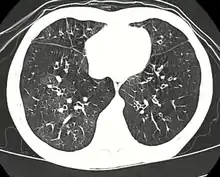

High resolution CT scan showing bronchiolitis obliterans with mosaic attenuation, bronchiectasis, air trapping and bronchial thickening[3] | |

Early in the disease chest radiography is typically normal but may show hyperinflation.[6] As the disease progresses a reticular pattern with thickening of airway walls may be present.[4][6] HRCT can also show air trapping when the person being scanned breathes out completely; it can also show thickening in the airway and haziness in the lungs.[11] A common finding on HRCT is patchy areas of decreased lung density, signifying reduced vascular caliber and air trapping. This pattern is often described as a "mosaic pattern", and may indicate bronchiolitis obliterans.[6]